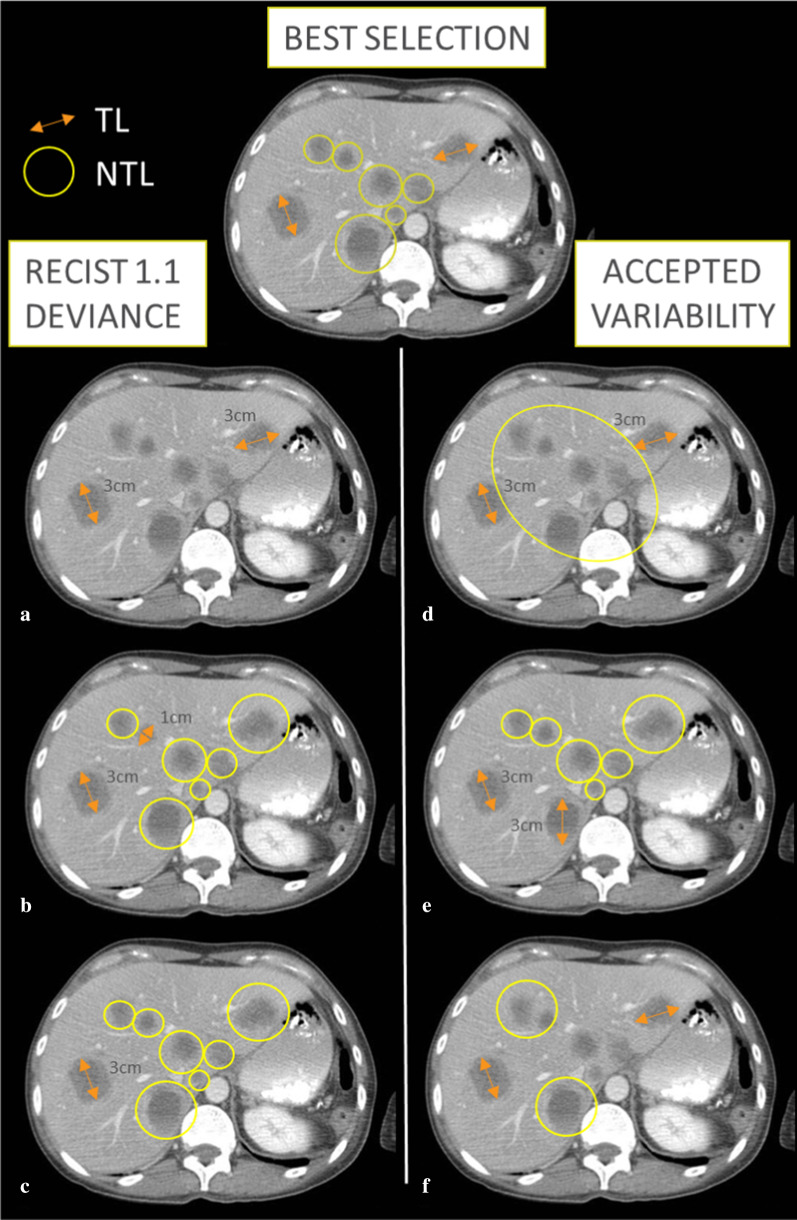

In addition to equivocal lesions as shown in Fig. 1 for a given disease presentation, there exists a wide variety of lesion selection patterns, all complying with RECIST recommendations (Fig. 2) [1, 1].

Fig. 2.

RECIST 1.1 baseline selection accepted variability and errors. TL: Target Lesions are measured by double arrows, NTL: Non-Target Lesions are circled. This patient had a disease limited to the liver. We illustrate 3 different types of baseline lesion selection that can be considered as errors and that deviate from RECIST guidance: a if no NTL have been selected; b if the smallest Target Lesions have been selected instead of the largest; c if only 1 TL has been selected while 2 were measurable. We illustrate 3 different lesion poolings that can be considered as variations from the ideal selection without deviating from the RECIST guidelines: d if NTL lesions are grouped inside an organ; e if different TL are chosen within the largest lesions; f if fewer NTL are selected considering the evaluation as categorial and qualitative even though, preferably, they should all be recorded but practically it is not always possible.